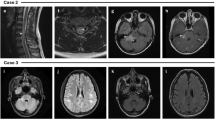

Younger patients (<5 years) tend to present with larger lesions, including tumefactive lesions (>2 cm). They also tend to have a wider distribution of lesions, including rare involvement of the corpus callosum [14, 34, 35]. The leukodystrophy-like pattern is rarely observed, particularly in very young patients presenting with MOGAD ADEM [22, 36,37,38]. On imaging, there are extensive confluent and often symmetric T2/FLAIR-hyperintense lesions in the cerebral white matter, associated with nodular enhancement (Fig. 3).

Magnetic resonance images show a leukodystrophy-like pattern in a 4-year-old girl with myelin oligodendrocyte glycoprotein antibody seropositivity, who presented with acute disseminated encephalomyelitis. a Coronal T2-weighted image shows bilateral confluent hyperintense signal changes involving asymmetrically the white matter. b Coronal fat-suppressed contrast-enhanced T1-weighted image shows bilateral nodular enhancement of the involved white matter (arrows). c Mid-sagittal T2-weighted image shows a small hyperintense lesion in the body of the corpus callosum (arrow)

Autoimmune encephalitis

This entity was first described in 2017 [51] and is commonly associated with fever, headaches, and seizures. Intra-cranial hypertension can accompany this phenotype [26, 52]. There is a higher prevalence in children, being reported in 12/89 (13.5%) pediatric-onset MOGAD, compared to 7/196 (3.6%) adults with MOGAD [53]. Three main patterns have been described: (1) Cortical encephalitis – also termed FLAIR-hyperintense lesions in anti-MOG encephalitis with seizures (FLAMES) [51, 54, 55]. On brain MRI, the T2/FLAIR-hyperintense cortical lesions can be unilateral or bilateral, diffuse, or focal. These lesions can involve the juxtacortical white matter and might be associated with leptomeningeal enhancement and/or diffusion restriction [45, 51, 53, 55] (Fig. 7). Other reported findings include swelling of the cortex with effacement of the sulci [56] (Fig. 8). Unilateral involvement affects more commonly the frontal and parietal lobes, while bilateral involvement affects commonly the frontal lobes. The occipital lobes are rarely involved [22, 55, 56]. (2) Basal ganglia encephalitis – radiological findings include bilateral high T2/FLAIR signal involving the basal ganglia and/or thalami [15, 26] (Fig. 9). In a large prospective Spanish study, among 64 patients with autoimmune encephalitis (other than ADEM), MOG antibodies were more common than all other neuronal antibodies combined (33%), even more common than anti-N-methyl-D-aspartate receptor (NMDAR) encephalitis [26]. Of note, in rare cases, MOGAD-encephalitis may coexist either simultaneously or in succession with anti-NMDAR encephalitis [22, 26, 57, 58]. (3) Meningoencephalitis/aseptic meningitis with leptomeningeal enhancement – may be seen at presentation of MOGAD in 33–46% of patients [59, 60], even without evidence of demyelination, or may precede demyelination [61], and may be the only radiological finding in MOG antibody-associated aseptic meningitis [55, 62]. On imaging, unilateral or bilateral leptomeningeal enhancement is observed (Fig. 8), and the underlying cortex may be preserved (Fig. 9). In a retrospective cohort of 42 pediatric patients with MOGAD, POMS, and AQP4+NMOSD [63], leptomeningeal enhancement was only seen in MOGAD patients (6/20, 30%). Acquiring contrast-enhanced FLAIR sequences might be helpful for leptomeningeal enhancement detection [64, 65].

Lesion dynamics in myelin oligodendrocyte glycoprotein antibody-associated disease (MOGAD). a-d, f Axial fluid-attenuated inversion recovery (FLAIR) and (e) axial contrast-enhanced T1-weighted magnetic resonance images of the brain, obtained from a 2-year-old boy, who presented with a single focal seizure. a MR image at initial presentation shows very subtle subcortical FLAIR hyperintensities (arrow). The child developed progressive neurological deterioration a month after initial presentation, including behavioral changes and visual impairment, and was diagnosed with acute disseminated encephalomyelitis (ADEM). MR image obtained at 1-month interval shows characteristic findings of ADEM, including bilateral, diffuse, confluent, and poorly demarcated white matter signal changes distributed asymmetrically with involvement of the basal ganglia and thalami. Serology confirmed myelin oligodendrocyte glycoprotein antibodies. The evolvement of symptoms and radiological findings is typical of MOGAD fluctuation during the same neurological attack. c MR image obtained at 6-months post-attack shows a near-complete resolution of the radiological findings. The patient was asymptomatic and his myelin oligodendrocyte glycoprotein antibody titers were negative. d MR image obtained at 21-month follow-up shows a new “silent” hyperintense lesion in the left parietal deep and juxta-cortical white matter (arrow), (e) associated with nodular enhancement (arrow). Due to myelin oligodendrocyte glycoprotein antibody seroconversion at that time, the patient started on a monthly maintenance therapy. f MR image obtained at 30-month post-attack shows interval resolution of the “silent” lesion shown on (d, e)

Lesion dynamics in myelin oligodendrocyte glycoprotein antibody-associated disease. a-c Magnetic resonance images of the brain obtained from an 11-year-old girl who presented with headache and vomiting, and was seropositive to myelin oligodendrocyte glycoprotein antibodies. a, b Axial fluid-attenuated inversion recovery (FLAIR) images show focal increased signal in the left thalamus (arrow in a), with diffuse sulcal effacement (b). c Axial contrast-enhanced T1-weighted image shows bilateral leptomeningeal enhancement. d-f MR images obtained at 3-month post-attack. d, e Axial FLAIR images show interval resolution of the signal abnormality in the left thalamus (d), with normal appearing sulci (e). f Axial contrast-enhanced T1-weighted image shows interval resolution of leptomeningeal enhancement. However, there are new subcortical increased FLAIR signal lesions (arrows in e) that are likely representing radiological lag phenomenon, as the patient was asymptomatic at that time. g, h Axial FLAIR and (i) axial contrast-enhanced T1-weighted images, obtained at 4-year post-attack, show normal appearance of the brain. This patient did not receive maintenance therapy